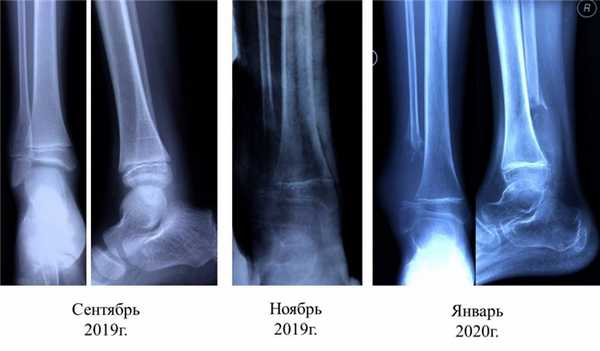

Рентгенологически различают два типа аневризмальной кисты - расположенные центрально и эксцентрически. В течение аневризмальных кист выделяют три фазы - остеолиза, отграничения и восстановления.

КТ позволяет выявить характерный для аневризмальной кисты симптом “горизонтальных уровней”, а также относительную плотность для уточнения тактики лечения.

Для уточнения диагноза выполняют рентгенологическое исследование пораженного сегмента: рентгенографию бедренной кости, рентгенографию плечевой кости и т. д. На основании рентгенологической картины определяют фазу патологического процесса. В фазе остеолиза на снимке обнаруживается бесструктурное разрежение метафиза, соприкасающееся с зоной роста. В фазе отграничения на рентгенограммах видна полость с ячеистым рисунком, окруженная плотной стенкой и отделенная от зоны роста участком нормальной кости. В фазе восстановления на снимках выявляется участок уплотнения костной ткани или небольшая остаточная полость.

Различают две формы аневризмальных костных кист: центральную и эксцентрическую. В течении болезни выделяют такие же фазы, как и при солитарных кистах. Клинические проявления достигают максимума в фазе остеолиза, постепенно уменьшаются в фазе отграничения и исчезают в фазе восстановления. На рентгенограммах в фазе остеолиза выявляется бесструктурный очаг с внекостным и внутрикостным компонентом, при эксцентричных кистах внекостная часть по размеру превышает внутрикостную. Надкостница всегда сохранена. В фазе отграничения между внутрикостной зоной и здоровой костью образуется участок склероза, а внекостная зона уплотняется и уменьшается в размере. В фазе восстановления на рентгенограммах обнаруживается участок гиперостоза или остаточная полость.